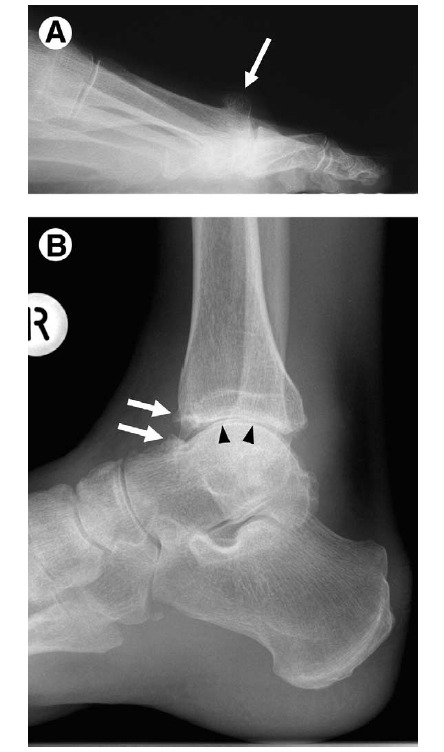

Figure 7 Calcaneal fracture.

(A) Achilles avulsion. Along with anterior process fracture depicted in Fig. 5E and extensor digitorum brevis avulsion fracture shown in Fig. 5B, Achilles tendon avulsion (arrow) is classified as an “extraarticular” calcaneal fracture. This fracture is more common in diabetic patients and patients with renal osteodystrophy.

(B) Joint depression-type fracture. Resulting from axial load injury, the “joint depression type” is the most common of the “intraarticular” calcaneal fractures. The talus is driven into the calcaneus, displacing the subtalar articular surface into the calcaneal body, flattening Boehler’s angle (lines), and typically creating an anteromedial sustentaculum fragment

and a posterior tubercle fragment, with varying degrees of comminution and medial-to-lateral widening. The “tonguetype

fracture” is described when a curvilinear fragment extending to the posterosuperior calcaneus is rotated downward.